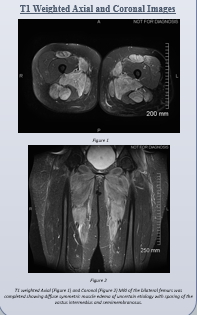

Case Presentation: 18-year-old female college student with a past medical history of polycystic kidney disease, febrile seizures and treated Kawasaki’s disease presented with bilateral lower extremity muscle weakness, which was acute and uniform without any patterns such as ascending or descending quality. The severity of the symptoms lead to patient’s inability to ambulate without support over the past week.The patient also complained of nausea and vomiting and cough with yellow sputum and dyspnea. In the ED, physical exam was positive for bilateral decreased motor strength of 3/5 of proximal lower extremities, however sensation was intact and 2+ pulses palpable. Mild wheezing was noted on auscultation of bilateral lung fields, more prominent on the right side. Patient also had diffuse tenderness to palpation of the abdomen. Patient’s vitals were HR of 130 bpm, BP of 100/52 mmHg, T of 98F, RR of 18 breaths/min and SaO2 of 99% on RA. The patient was found to have creatine kinase (CK) greater than 200,000 IU/L with ALT of 533 IU/L and AST of 1825 IU/L, and elevated troponin of 0.047 ng/mL. Other significant lab values was a creatinine of 1.54 mg/dL and D-dimer of 7,691 ng/mL FEU. Patient was started on aggressive crystalloid therapy with frequent monitoring of CK and CMP. After extensive rheumatological work up for autoimmune sources of myositis was ruled out, patient muscle biopsy confirmed myositis given the tissue showed inflammation and necrosis. Infectious evaluation eventually showed that the patient was serologically positive for Epstein Barr Virus, Parainfluenza Type 2, and Coxsackie B virus. The patient was discharged with great clinical improvement and improvement of lab values.